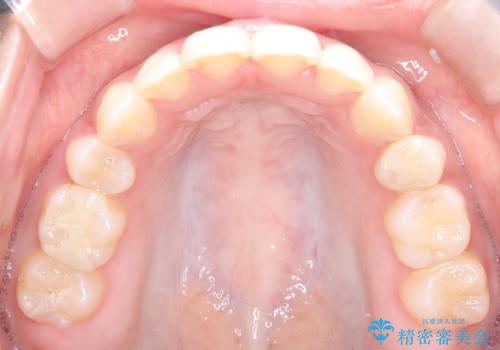

【インビザライン】シザーズバイト、抜歯矯正

- オープンバイトを主訴に来院された患者様です。

抜歯を行うことで、インビザラインを用いて前歯を下げることができ、同時にオープンバイトを改善することができました。

今回はインビザラインのみで治療を終了することができました。